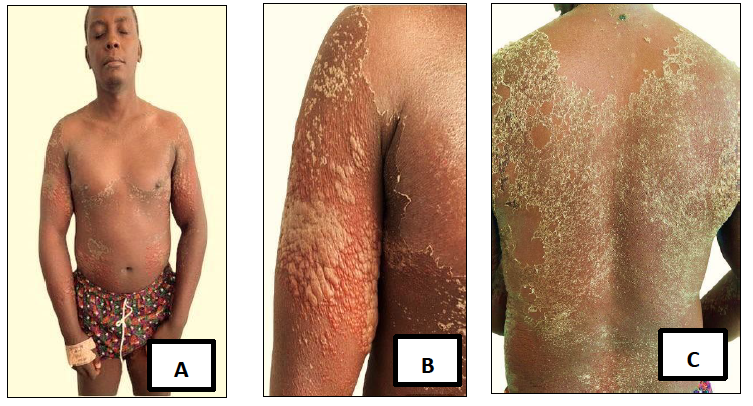

Casos clínicos